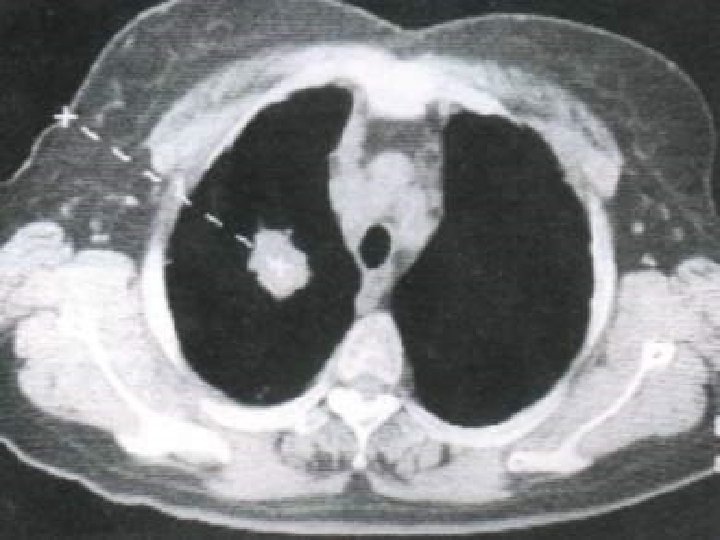

DIAGNOSIS 1. 2. 3. 4. 5. 6. 7. 8. 9. 10. x-ray examination. CT chest. MRI chest cytological examination of sputum. Bronchoscopic examination. Mediastinoscopy. Needle biopsy. Percutaneous transthoracic Lymph nodes biopsy. Supraclavicular, cervical, axillary. Pleural effusion examination. Thoracic exploration.

(Obstructive atelectasis)